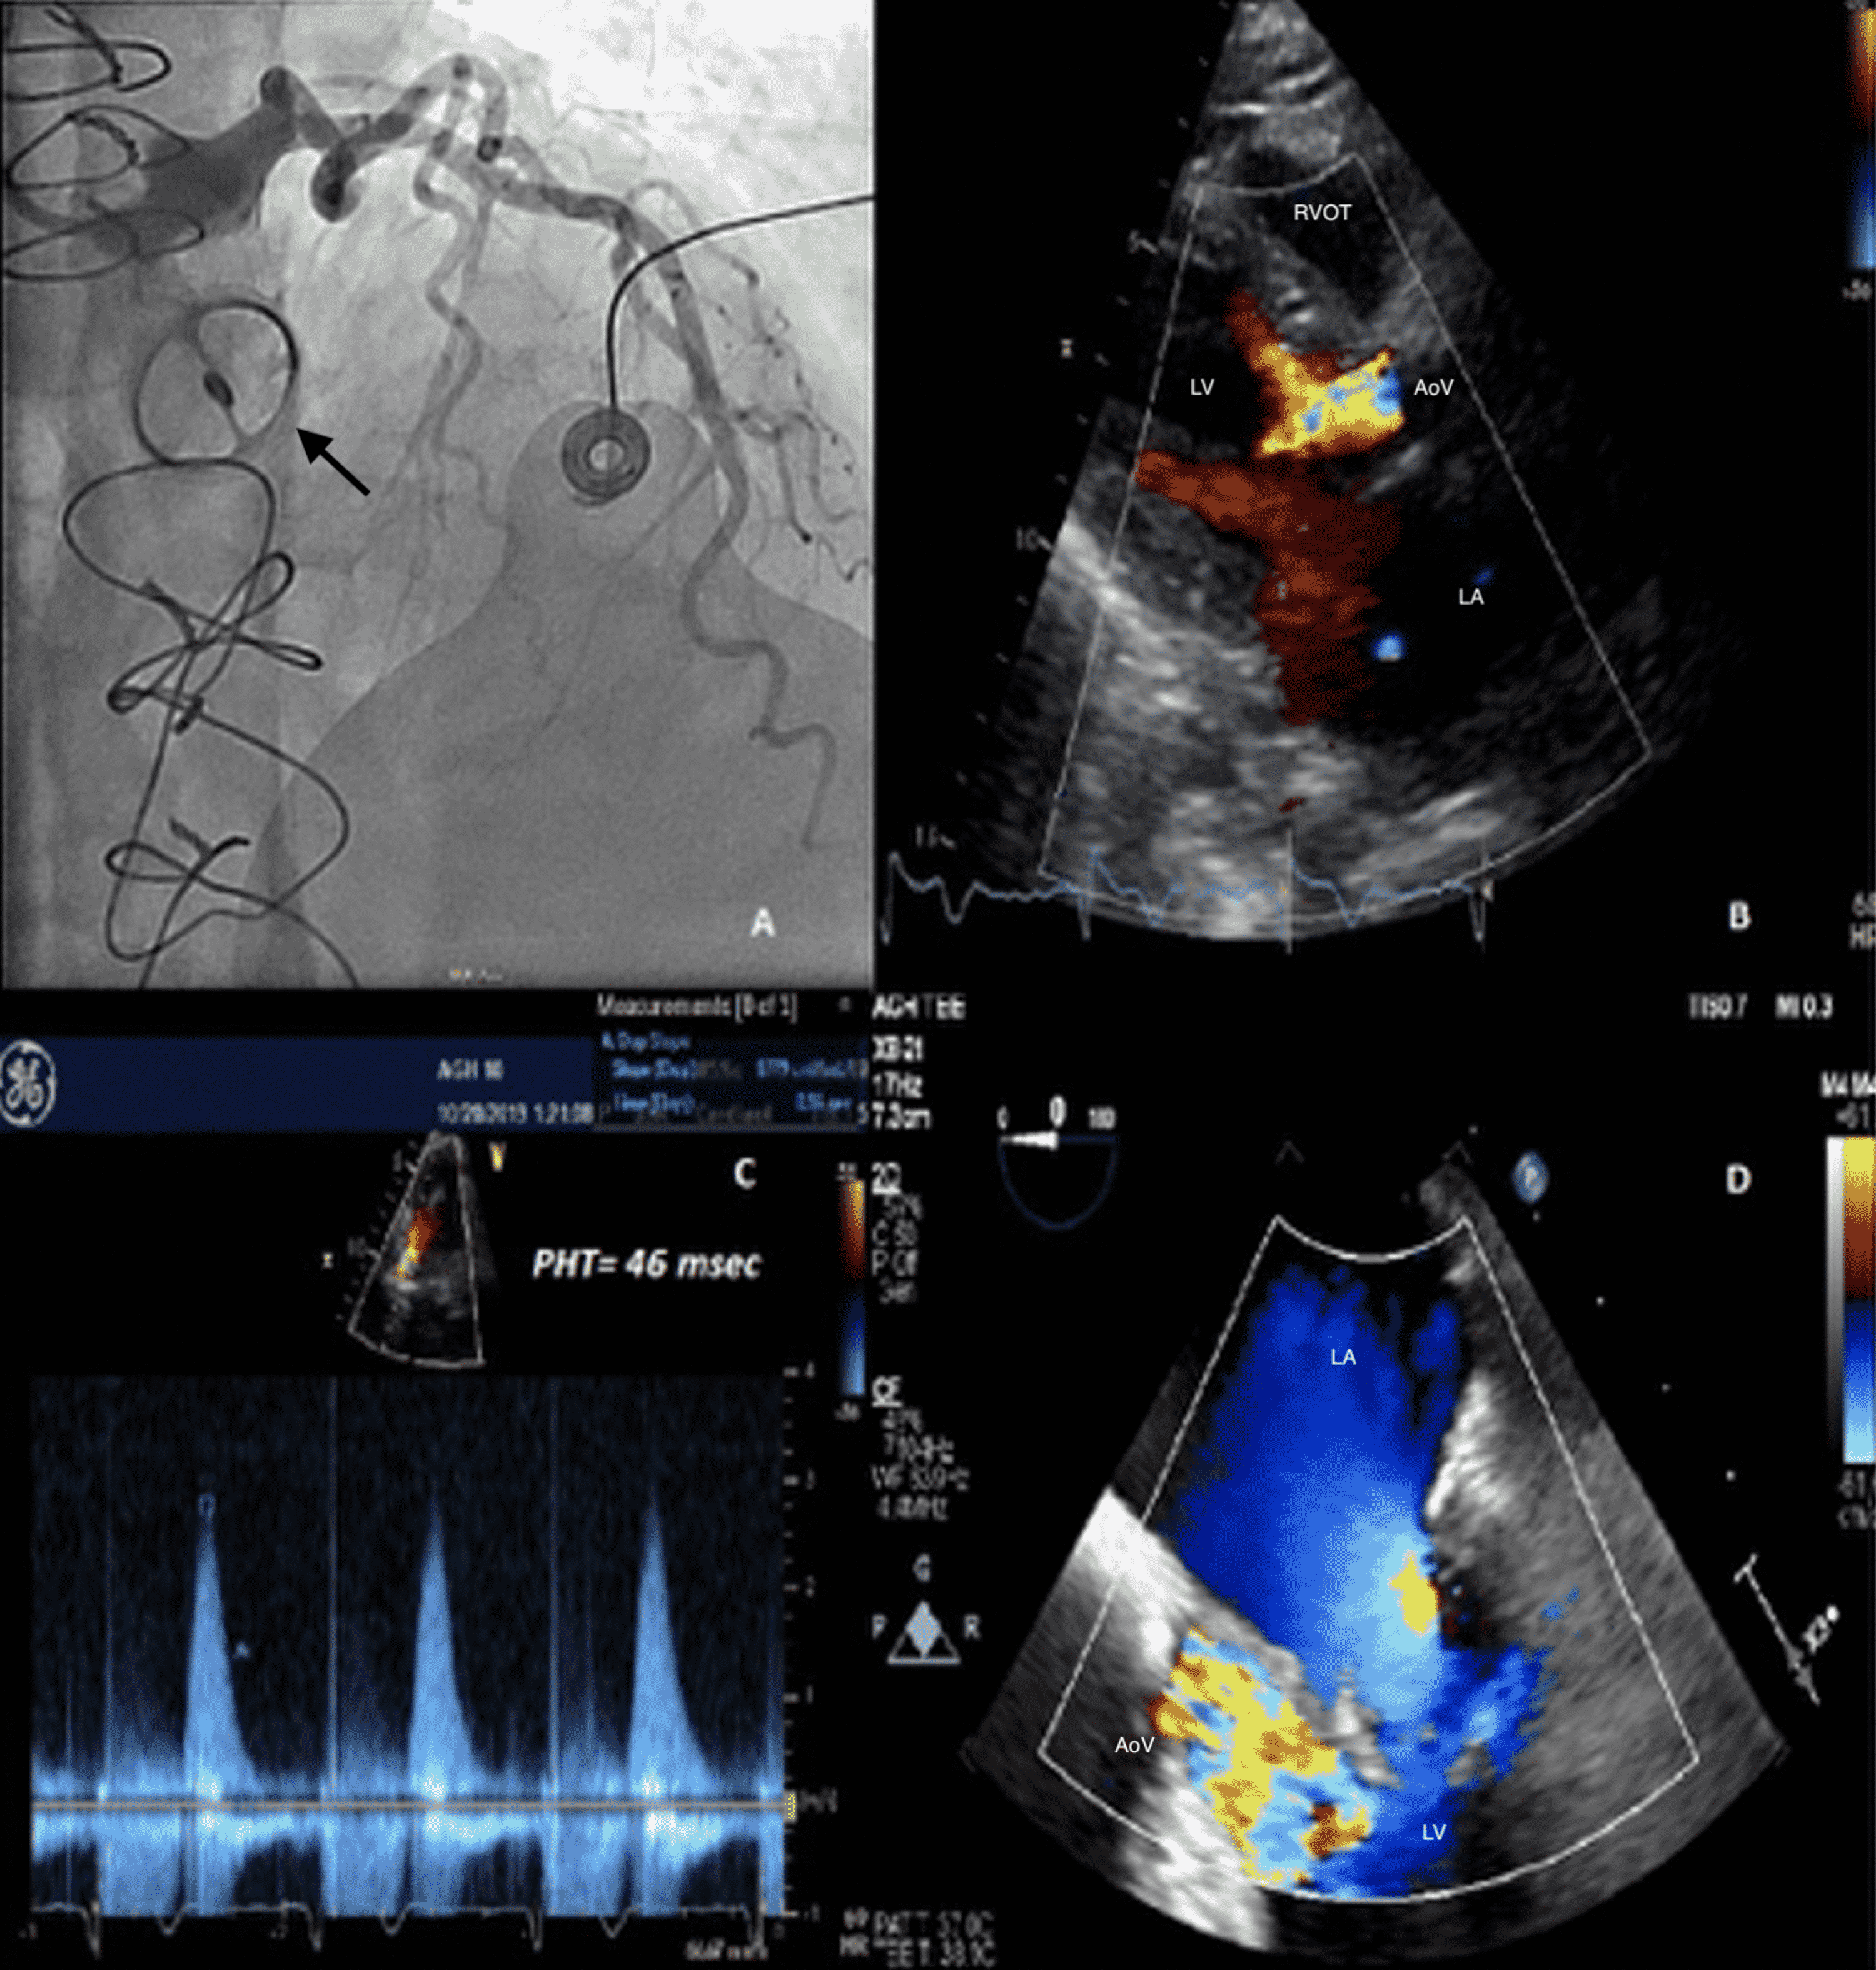

Split screen echocardiographic image in parasternal long axis view Washing Jet Echo A comprehensive guide to echocardiographic assessment of prosthetic valves, including types, complications, and parameters. • all mechanical valves display “normal” regurgitant jets, sometimes referred to as “washing jets.” these flows are thought to. Learn how to distinguish physiologic and pathologic. Mild regurgitant washing jets are apparent in normally functioning mechanical tpvs, while mild regurgitant transprosthetic. Washing Jet Echo.

Cureus Acute Severe Aortic Regurgitation From Catastrophic Pannus Washing Jet Echo Learn how to distinguish physiologic and pathologic. • all mechanical valves display “normal” regurgitant jets, sometimes referred to as “washing jets.” these flows are thought to. A comprehensive guide to echocardiographic assessment of prosthetic valves, including types, complications, and parameters. Mild regurgitant washing jets are apparent in normally functioning mechanical tpvs, while mild regurgitant transprosthetic. Washing Jet Echo.

Wellfunctioning mitral valve prosthesis with physiological jet (upper Washing Jet Echo A comprehensive guide to echocardiographic assessment of prosthetic valves, including types, complications, and parameters. Learn how to distinguish physiologic and pathologic. Mild regurgitant washing jets are apparent in normally functioning mechanical tpvs, while mild regurgitant transprosthetic. • all mechanical valves display “normal” regurgitant jets, sometimes referred to as “washing jets.” these flows are thought to. Washing Jet Echo.

Mitral regurgitation jet by color Doppler echocardiography Washing Jet Echo • all mechanical valves display “normal” regurgitant jets, sometimes referred to as “washing jets.” these flows are thought to. Learn how to distinguish physiologic and pathologic. A comprehensive guide to echocardiographic assessment of prosthetic valves, including types, complications, and parameters. Mild regurgitant washing jets are apparent in normally functioning mechanical tpvs, while mild regurgitant transprosthetic. Washing Jet Echo.